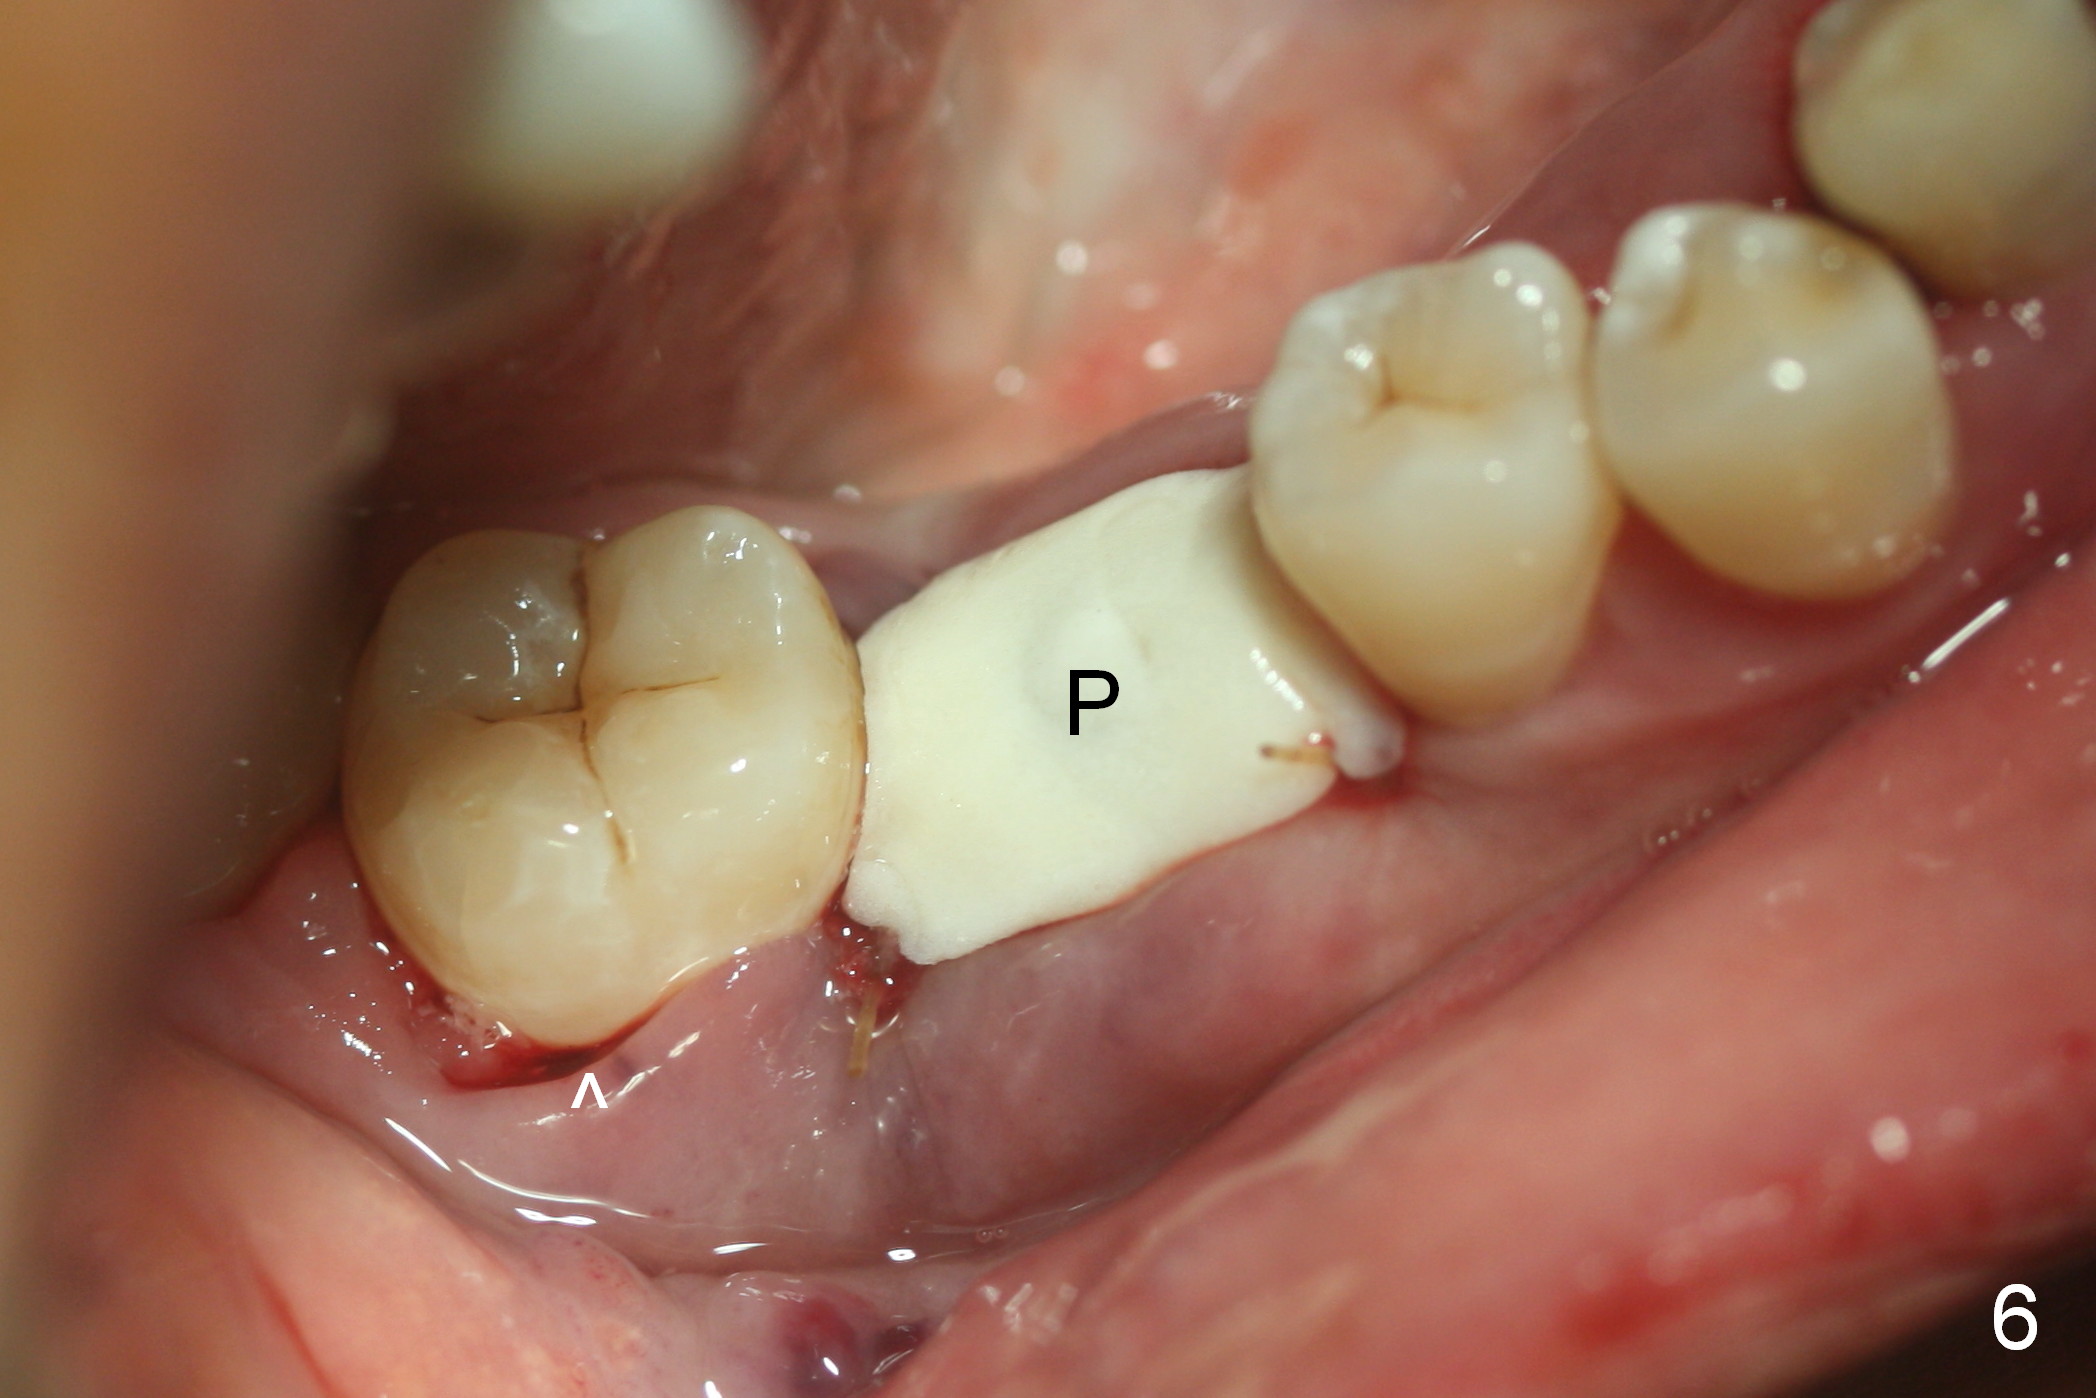

After cleaning the root surface with a surgical curette, a 1.6 mm pilot drill is used to start osteotomy (O) between the mesial (M) and distal (D) roots, followed by a marking bur and 3.8 mm Magic drill 13 mm deep (Fig.1,2). Following root removal, the 3.8 mm drill is reused for 11 mm (Fig.3). After deepening the osteotomy for another 2 mm, a 4.5x13 mm implant is placed with insertion torque of 50 Ncm, followed by allograft (*, .5-2 mm) and a 5x4(2) mm abutment (Fig.4,5). An immediate provisional is fabricated to close the socket (Fig.6 P (lock in)). The detached buccal gingiva (Fig.6 *) is kept in place by applying periodontal dressing (Fig.7 *). Red dashed lines in Fig.1, 3, 5 represents the superior border of the Inferior Alveolar Canal and Mental Foramen.